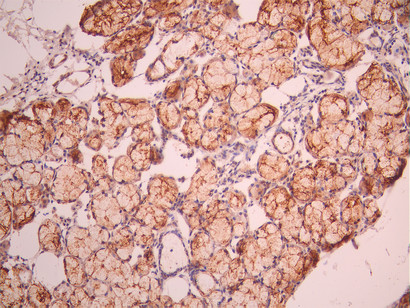

IHC image of CSB-RA192672A0HU diluted at 1:100 and staining in paraffin-embedded human endometrial cancer performed on a Leica BondTM system. After dewaxing and hydration, antigen retrieval was mediated by high pressure in a citrate buffer (pH 6.0). Section was blocked with 10% normal goat serum 30min at RT. Then primary antibody (1% BSA) was incubated at 4°C overnight. The primary is detected by a Goat anti-rabbit polymer IgG labeled by HRP and visualized using 0.05% DAB.